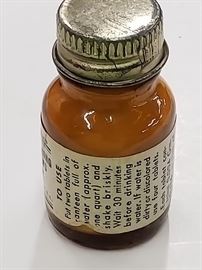

Lots 550-574 Political Lots 575-599 Books Lots 600-624 Art